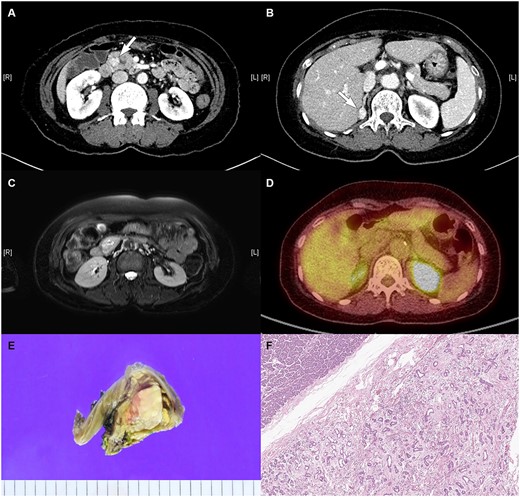

A 57-year-old female was referred to the outpatient department of our institute since an enhanced abdominopelvic CT conducted in another hospital showed (i) a 3.3-cm-sized hypervascular mass with internal cystic changes in the uncinate process of the pancreas and (ii) a 1.6-cm-sized enhancing fat-containing lesion in the right adrenal gland (Fig. 1a and b). At the initial outpatient consultation, the patient denied any specific symptoms. She had no noteworthy medical history except hypertension and dyslipidemia requiring medication. Her family history was notable for pancreatic cancer in her father and sister, gastric cancer in her brother, and type 2 diabetes mellitus in her mother.

Radiologic images of the (A) pancreatic mass in the uncinate process of the pancreas on CT, (B) right adrenal mass on CT, (C) pancreatic mass on MRI, and (D) pancreatic mass on PET. (E) Gross pathology: well-demarcated whitish to tan-colored mass with mild hemorrhage and (F) microscopic findings: variably cystic small to medium-sized ductular structures surrounded by collagenized stroma.

Magnetic resonance imaging (MRI) confirmed a 3.3-cm-sized hypervascular mass in the pancreas uncinate process and a 1.6-cm-sized enhancing fat-containing lesion in the right adrenal gland, corroborating the CT findings (Fig. 1c). PET-CT revealed increased fluorodeoxyglucose uptake with equivocal significance for malignancy between the pancreas head and duodenum and focal increased uptake in the right adrenal gland (Fig. 1d).